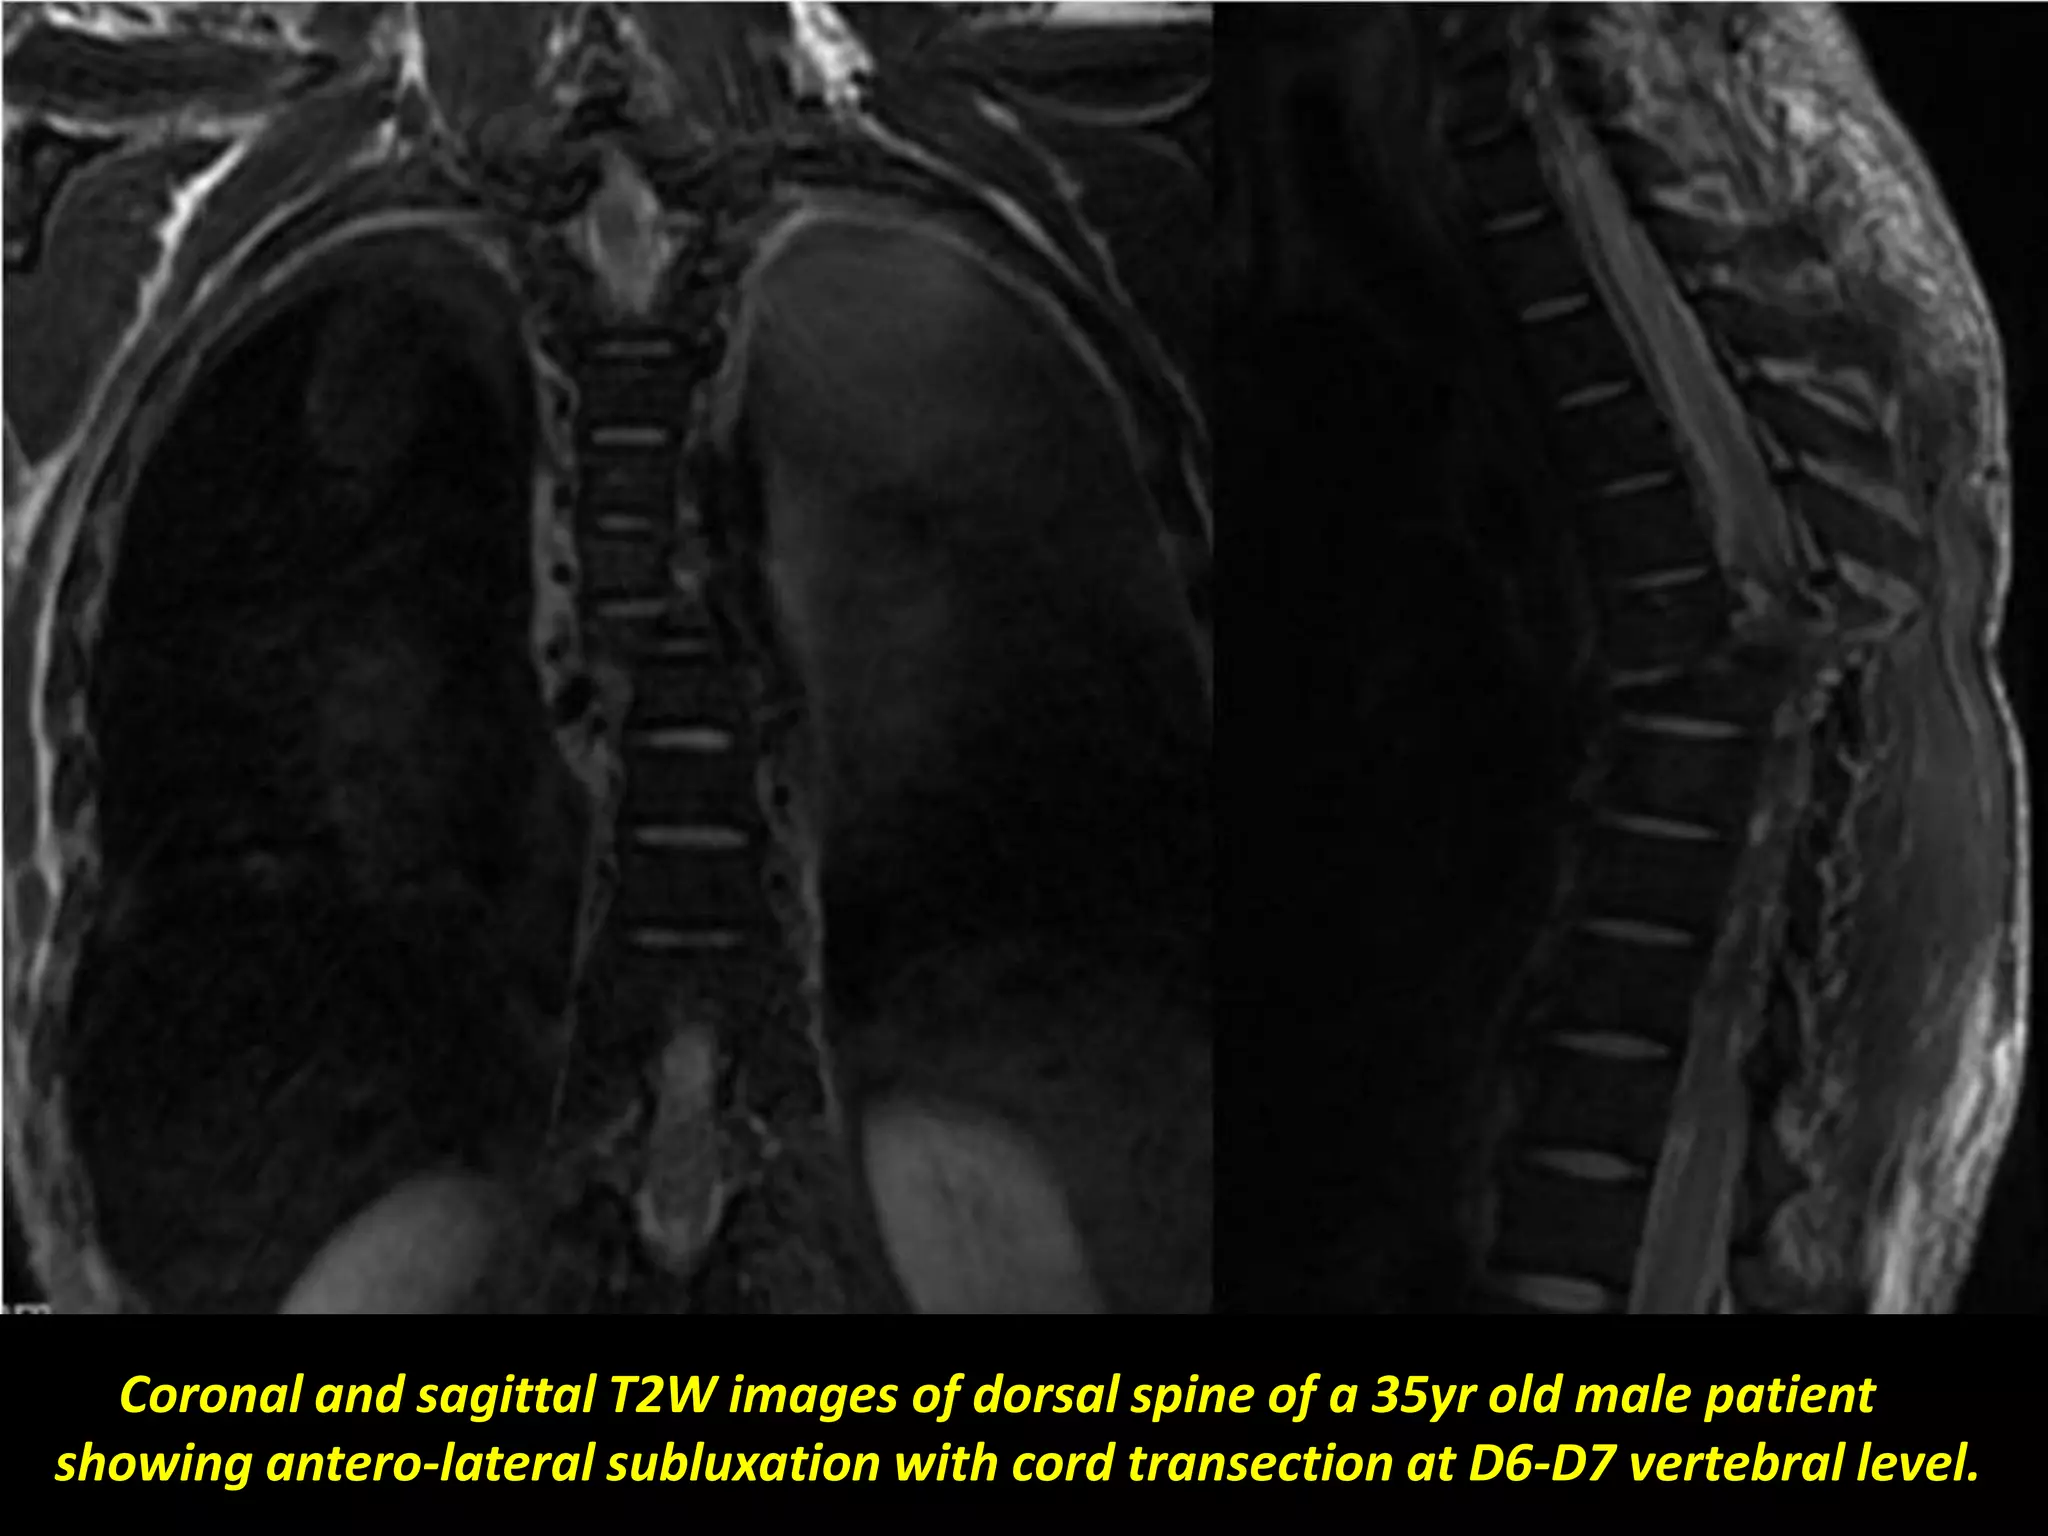

Sagittal T2W images of dorsal spine showing

complete cord transection (arrow).

Coronal and sagittal T2W images of dorsal spine of a 35yr old male patient

showing antero-lateral subluxation with cord transection at D6-D7 vertebral level.